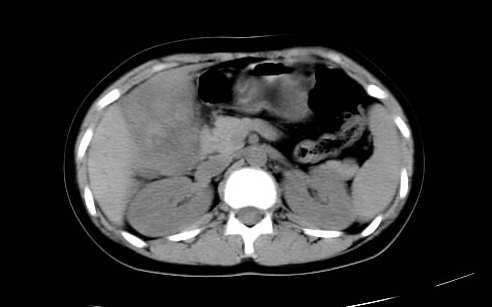

女 16岁  右上腹痛一天,无其他不适

肿块最大径位于十二指肠降段与水平段移行处,并且与肝脏压迹呈“0”形征,可以考虑位于肝外并与胃肠道关系紧密,考虑胃肠道间质瘤(gist)可能较大,须除外神经节起源肿瘤。

肿块与十二指肠关系密切,支持间质瘤诊断.肝脏与结肠均为受压改变.

右下腹巨大肿快,密度不均匀,内见坏死低密度区,边界清楚,与周边胀器明显有分界,未见强化,多考虑来源于间叶组织的良性肿物.

我坚决反对您的观点,该病例定位:横结肠肝曲与升结肠之间的肠系膜及部分肠壁。请看下图:

病灶巨大,少部分向肠腔内生长,大部分向长腔外生长。其密度不均匀,增强显示明显不均匀强化,并见有大片状始终不强化的不规则坏死液化区。虽然病灶中上部形态尚可,病人又如此年轻,但中下部形态、密度、强化特点强烈提示为恶性病灶。综上,我考虑本病例为:恶性胃肠道间质瘤。